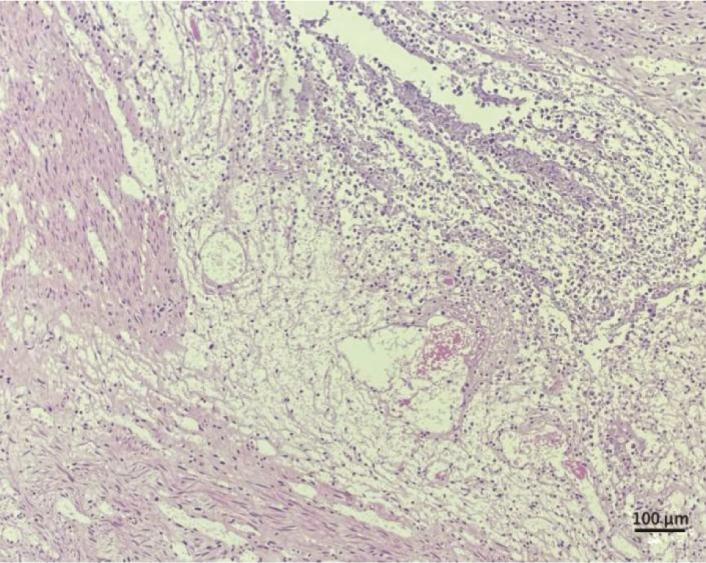

ZHU Ran-ran, YU Chun-li.

A Case of Malignant Mesothelioma of the Pelvic Peritoneum

[J]. Journal of International Obstetrics and Gynecology, 2025, 52(5): 508-511.